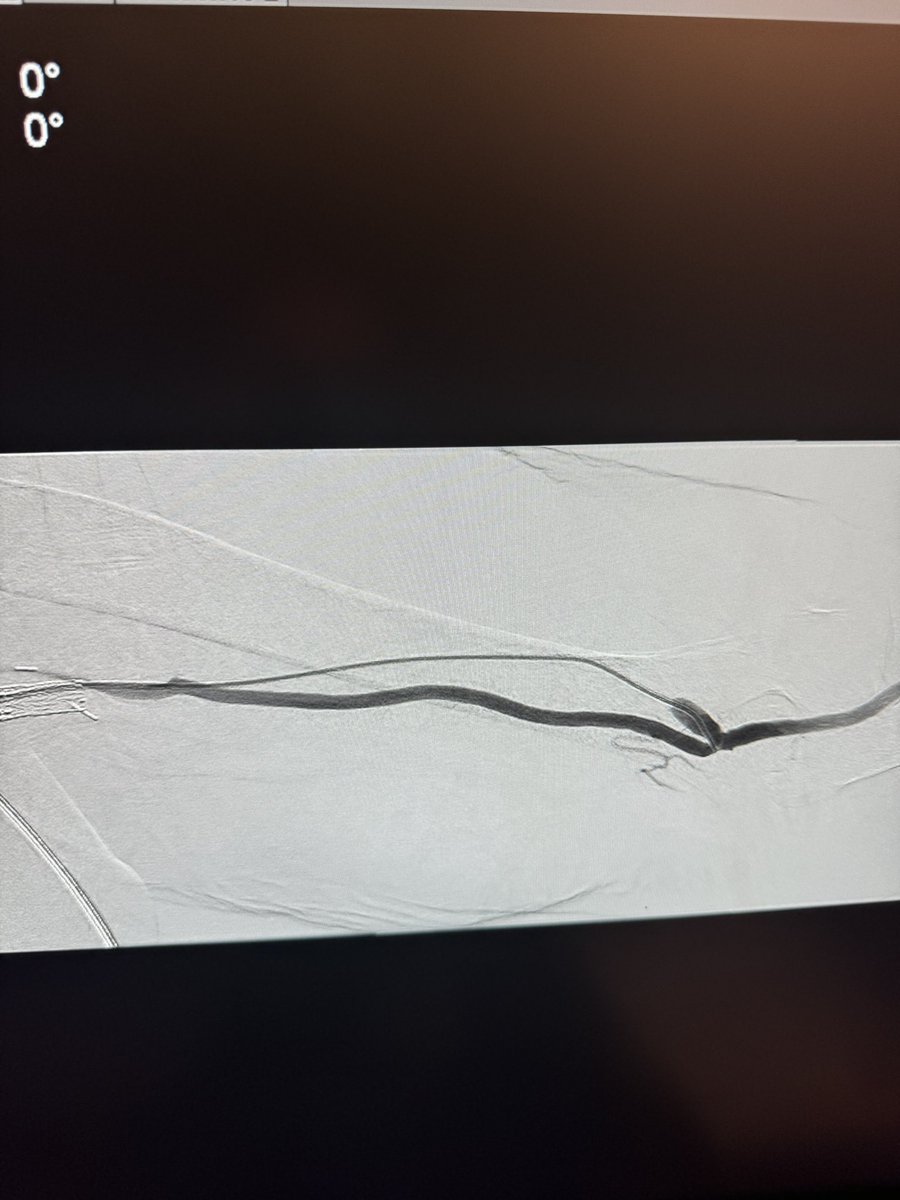

Here is what we did: VBX lower pole, sacrificed upper pole, coil packing. Very hostile abdomen - no open surgery. Neck too wide for coils alone. Normal contra kidney and function. @doc_ponraj Full video to follow on YouTube.